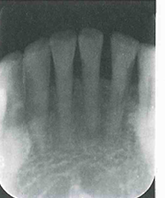

【影像学表现】牙髓钙化X线表现有两种类型,一是局限性,表现为髓石;一是弥散性,表现为髓室及根管钙化。局限性髓石与髓室形状有一定关系。后牙髓石往往表现圆形或卵圆形,大小不一。髓石可游离于髓室内,也可附着于髓室壁。前牙髓室较小,髓石可呈条状或针状充满于髓室及根管内,其周围有线状低密度影像围绕。弥散性牙髓钙化表现为正常髓室及根管影像完全消失,不能辨别出髓腔界限。有的髓腔尚可见,但变得很细,这种情况通常影响牙髓和根管治疗。